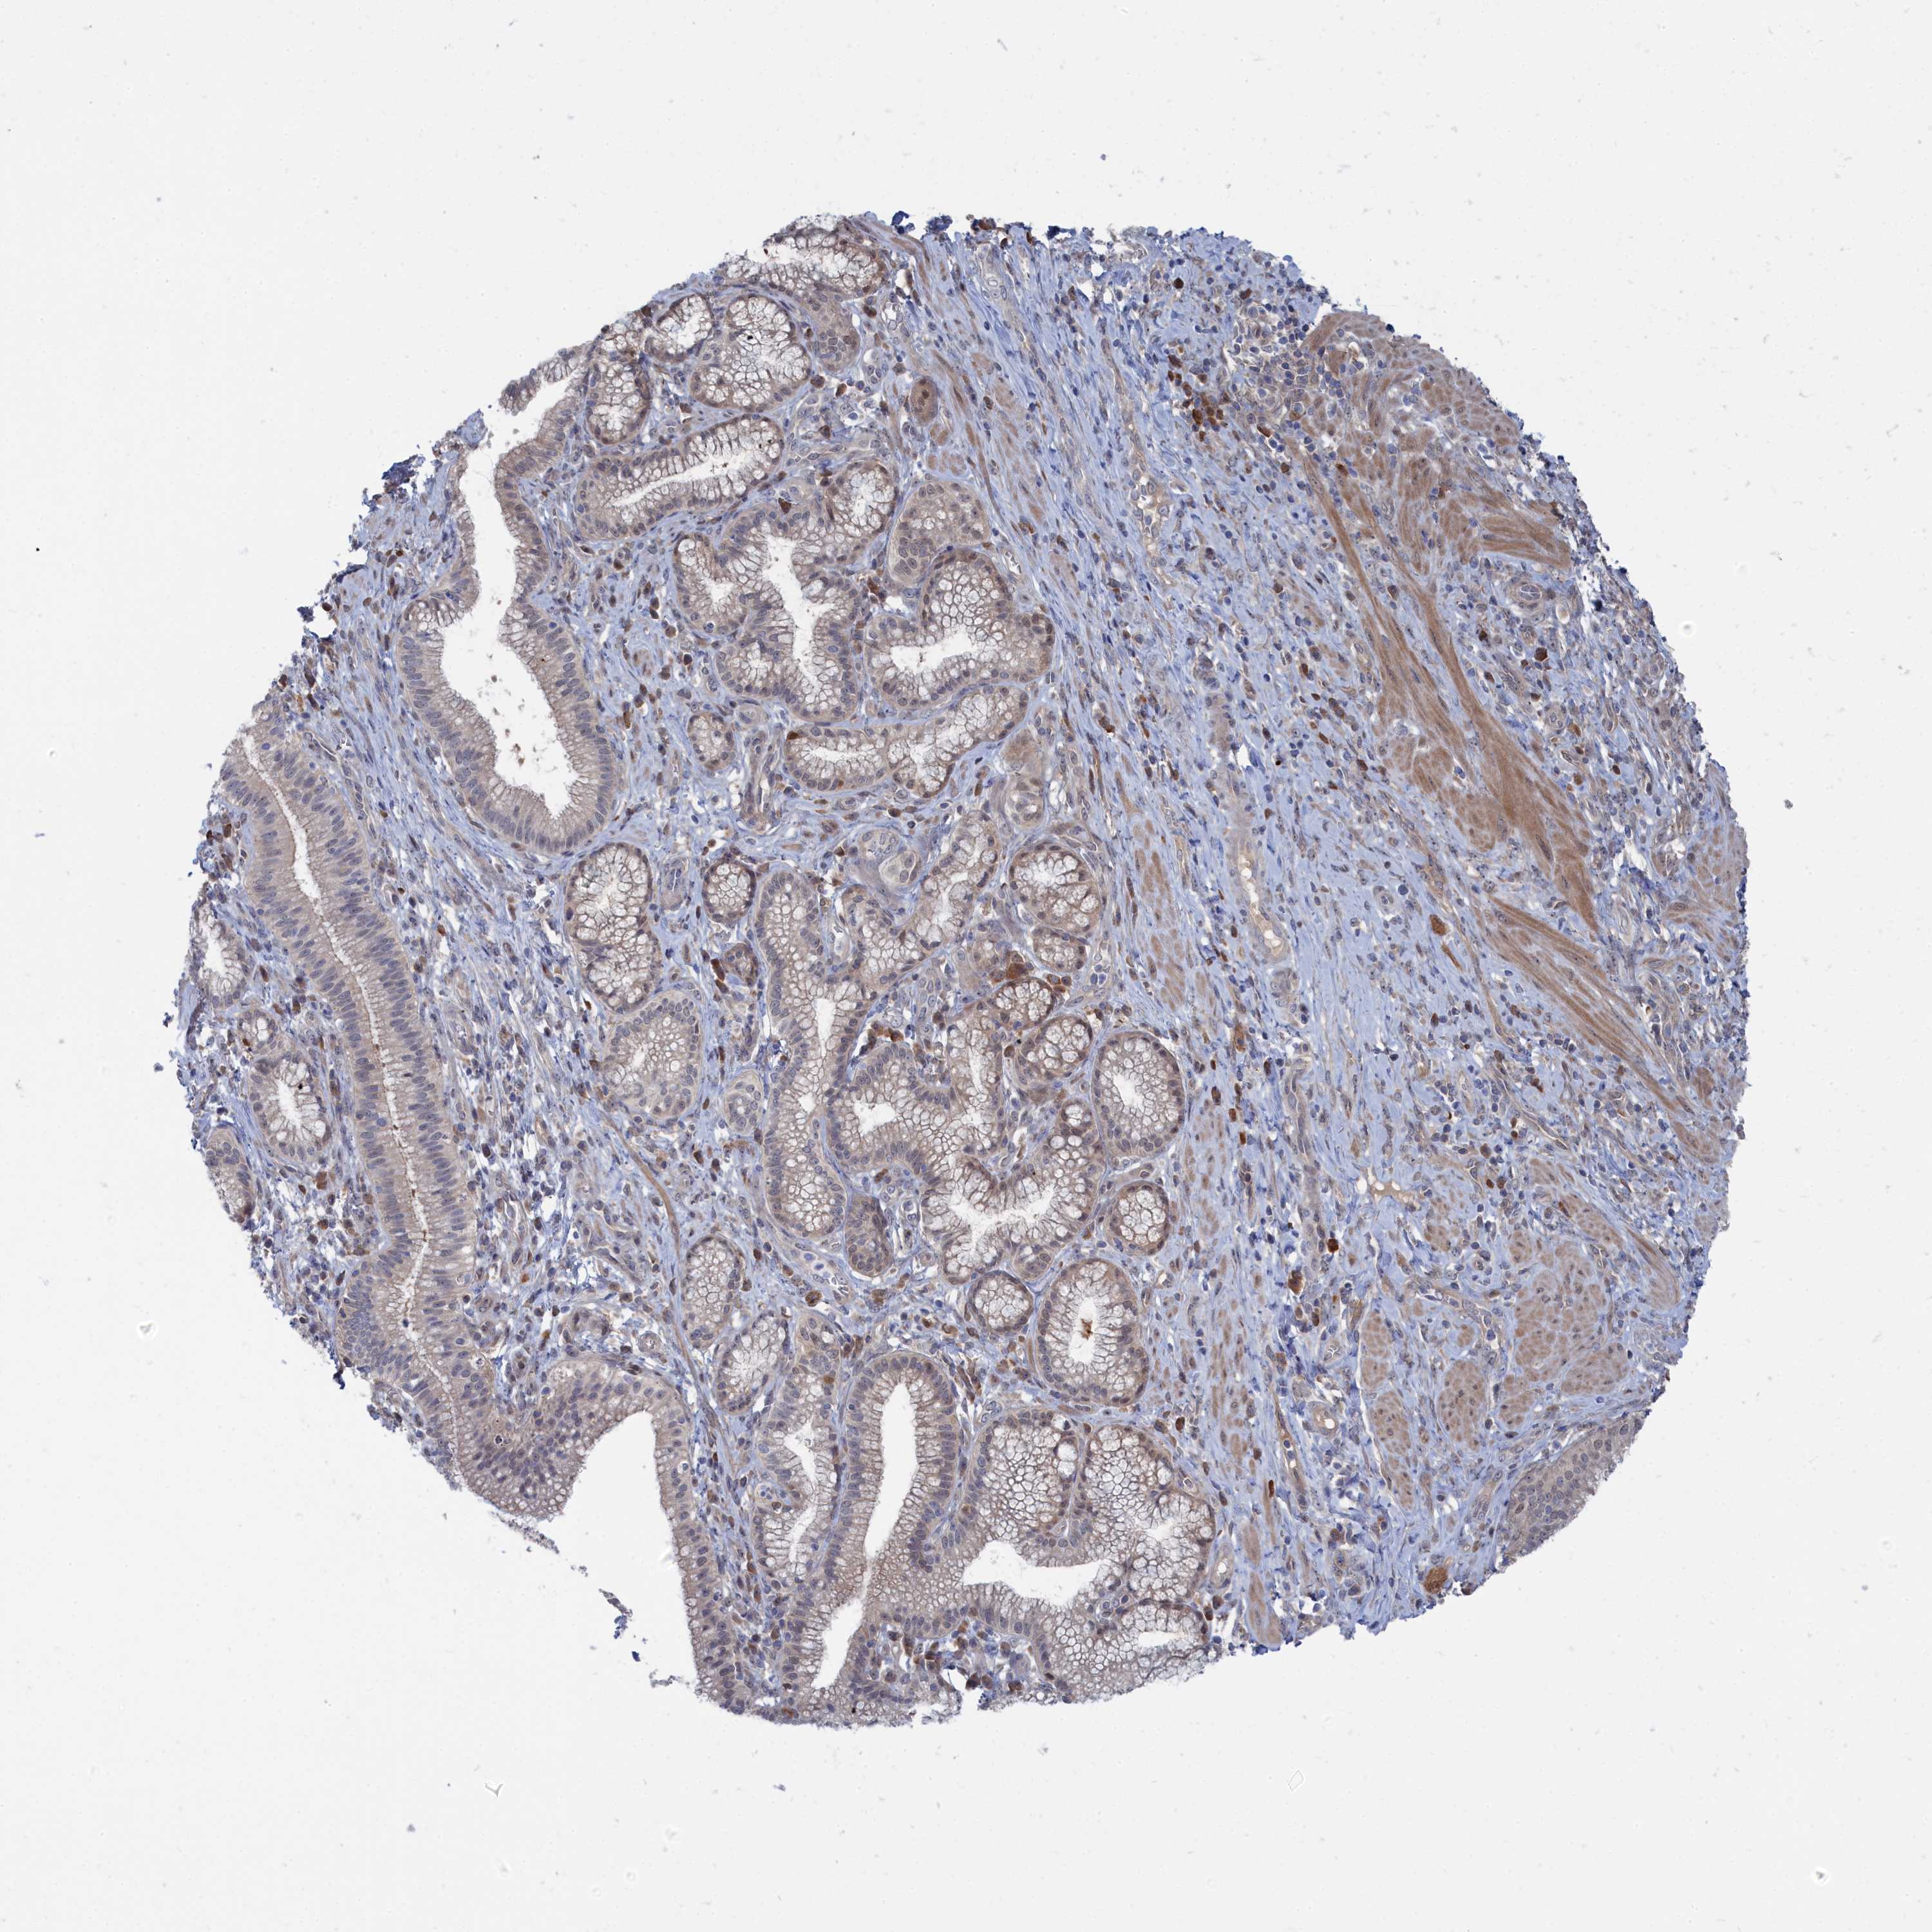

PANCREATIC CANCER - Protein expressioni

A mouse-over function shows sample information and annotation data. Click on an image to view it in a full screen mode. Samples can be filtered based on level of antibody staining by selecting one or several of the following categories: high, medium, low and not detected. The assay and annotation is described here.

Note that samples used for immunohistochemistry by the Human Protein Atlas do not correspond to samples in the TCGA dataset.

Antibody stainingi

Antibody staining in the annotated cell types in the current human tissue is reported as not detected, low, medium, or high, based on conventional immunohistochemistry profiling in selected tissues. This score is based on the combination of the staining intensity and fraction of stained cells.

Each image is clickable and will lead to virtual microscopy that enables deeper exploration of all samples and also displays staining intensity scores, fraction scores and subcellular localization as well as patient and tissue information for each sample.

Antibody HPA043254

Staining

High

Medium

Low

Not detected

Intensity

Strong

Moderate

Weak

Negative

Quantity

>75%

75%-25%

<25%

None

Location

Nuclear

Cytoplasmic/membranous

Cytoplasmic/membranous,nuclear

Adenocarcinoma, NOS